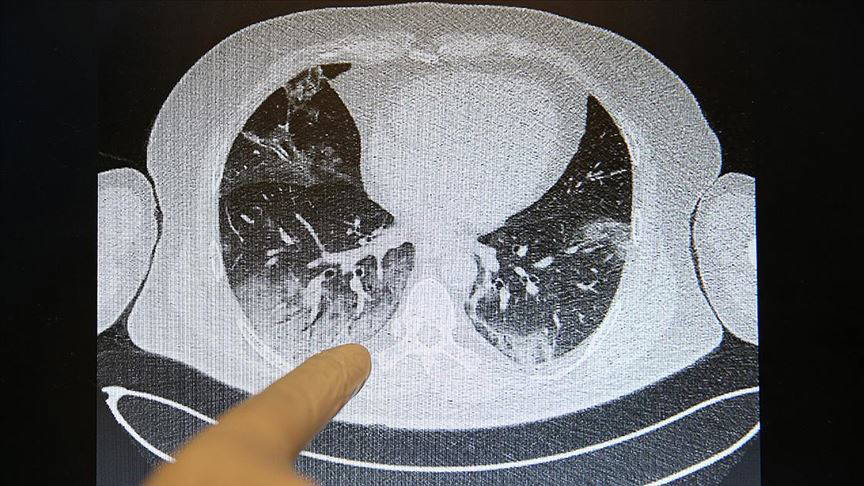

Akciğerlere verdiği tahribat nedeniyle solunum yetmezliği, nefes darlığı ve zatürreye neden olan yeni tip koronavirüsün (Covid-19) vücuda verdiği zarar, tomografi görüntüleriyle de ortaya konuluyor.

Özellikle nefes darlığı şikayetiyle başvurduğu hastanede akciğer tutulumu olduğu tespit edilen hastaların, tomografi görüntülerinde Covid-19'un verdiği tahribat ortaya çıkıyor.

Görüntülerdeki beyazlıklarla Covid-19'lu bir hastanın akciğerindeki tutulumlar, iltihap birikmeleri ve organın yapısının bozukluğu ortaya konuluyor. Normal hastaların ise akciğerindeki elastik yapı dikkati çekiyor.

Elastik yapıya sahip akciğerlerde Covid-19 nedeniyle oluşan tahribatlar sonucu zaman zaman organın kapasitesi küçüldüğü için hasta iyileştikten sonra da nefes almakta güçlük çekip, yürümekte zorlanabiliyor.